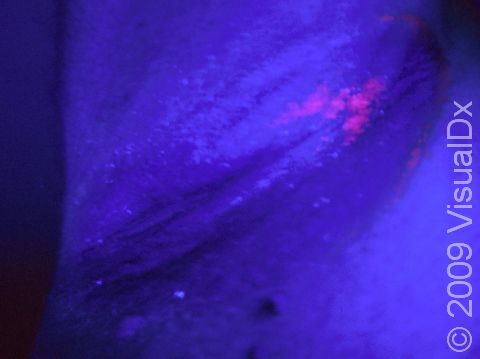

A Wood’s lamp is a device that emits ultraviolet (UV) light in the 365 nanometer range and is commonly used by dermatologists to assist in the diagnosis of various pigment and infectious disorders. The examination is performed in a dark room, allowing the Wood’s light to shine directly on the affected area for a few seconds and looking for any changes in color or fluorescence. Normal skin does not fluoresce under the light of a Wood’s lamp. If a fungal or bacterial infection or pigment disorder is present, Wood’s lamp examination can strengthen or lessen the suspicion of a particular diagnosis, based on the color of fluorescence of the affected skin being illuminated. In addition, subtle changes in color may be detected as well.

With the exam room lights turned off, the Wood’s lamp is held by the physician approximately 5 inches from the area being examined. The UV light emitted by the lamp is shined directly on the patient’s skin while the doctor looks for any colorful fluorescent changes that may suggest or confirm a particular diagnosis. This portion of the examination usually lasts less than a minute. Patients feel no discomfort from the exam.